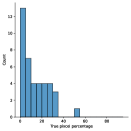

The main purpose of these experiments is to find the effect of using synthetic data generated from the SinGAN-Seg pipeline instead of small real datasets because the SinGAN-Seg pipeline can generate an unlimited number of synthetic samples per real image. A synthetic sample consists of a synthetic image and the corresponding ground truth mask. Therefore, experts’ knowledge is not required to annotate the ground truth mask. For these experiments, we have selected the best parameters of the SinGAN-Seg pipeline from the experiments performed under Section Synthetic data versus real data for segmentation. First, we created small sub-datasets from the real polyp images from fold one such that each dataset contains number of images, where can be one of the values of . The corresponding synthetic dataset was created by generating synthetic images and corresponding masks per real image. Then, our synthetic datasets consist of number of images such that . Then, we have compared true pixel percentages of real masks and synthetic masks generated from the SinGAN-Seg pipeline using histograms of bin size of . The histograms are depicted in Fig 10. The first row represents the histograms of real small detests, and the second row represents the histograms of corresponding synthetic datasets. Compare pairs (one from the top row and the corresponding one from the bottom) to get a clear idea of how the generated synthetic data improved the distribution of masks.